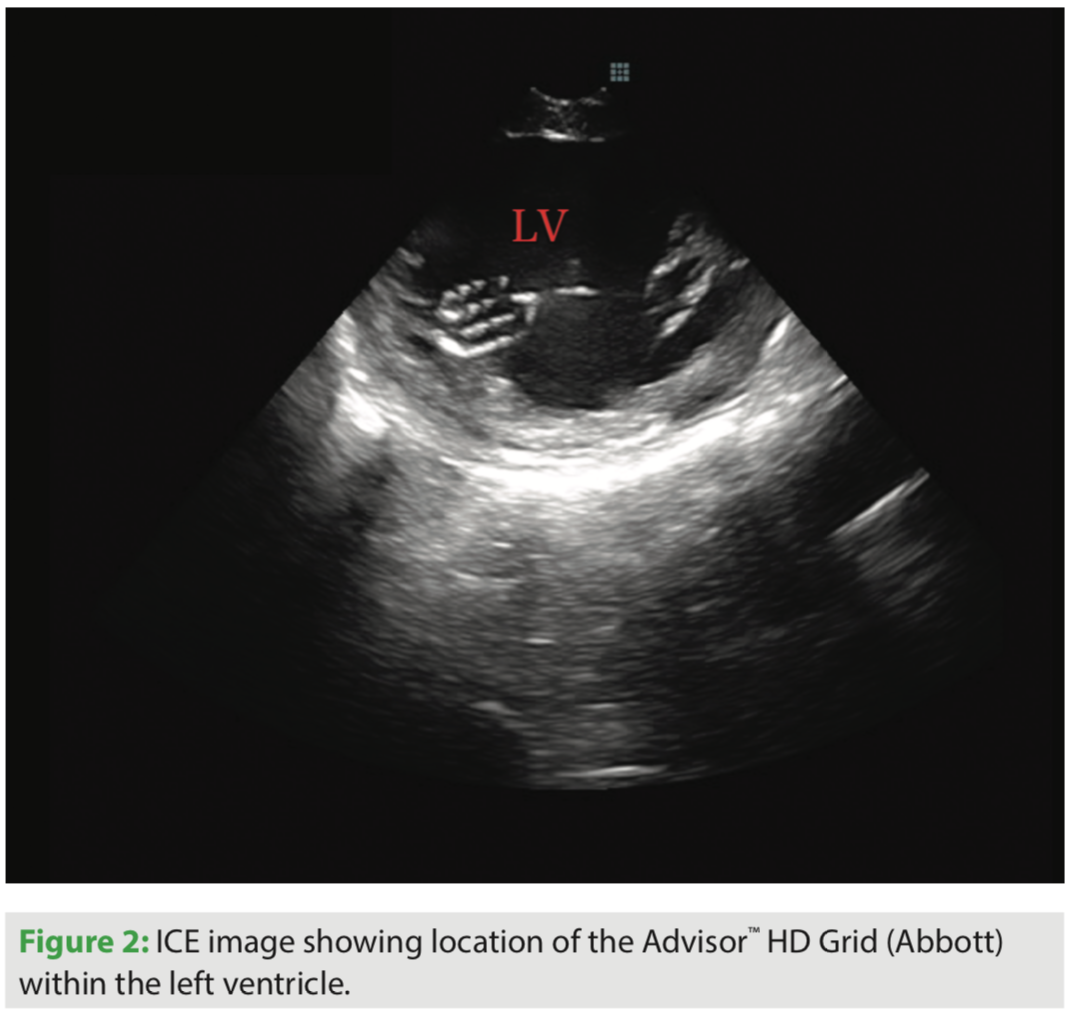

Beyond simply reducing fluoro exposure, I feel the use of ICE has significantly reduced my procedure time and complication rate, as well as improved my success rate. I use a number of non-standard views to optimize my ablation procedures. I routinely place the ICE catheter inside the left atrium for all left atrial procedures. If needed, for better visualization when addressing left ventricular tachyarrhythmias, I place the ICE catheter within the left ventricle. I frequently position the ICE catheter within the right ventricular outflow tract to address right ventricular outflow tract arrhythmias, and place the ICE catheter within the coronary sinus to improve visualization of the left atrium, left atrial appendage, and left ventricle.

I have been using the Advisor HD Grid for the past 6 months, and have been pleased with how this catheter has helped create detailed maps in a relatively short amount of time. I have found this catheter to be particularly useful for ablation of ventricular tachycardia and atrial tachycardia. I recently performed ablation of a PVC originating from the posteromedial papillary muscle and found that use of this catheter resulted in rapid acquisition of a very accurate activation map.